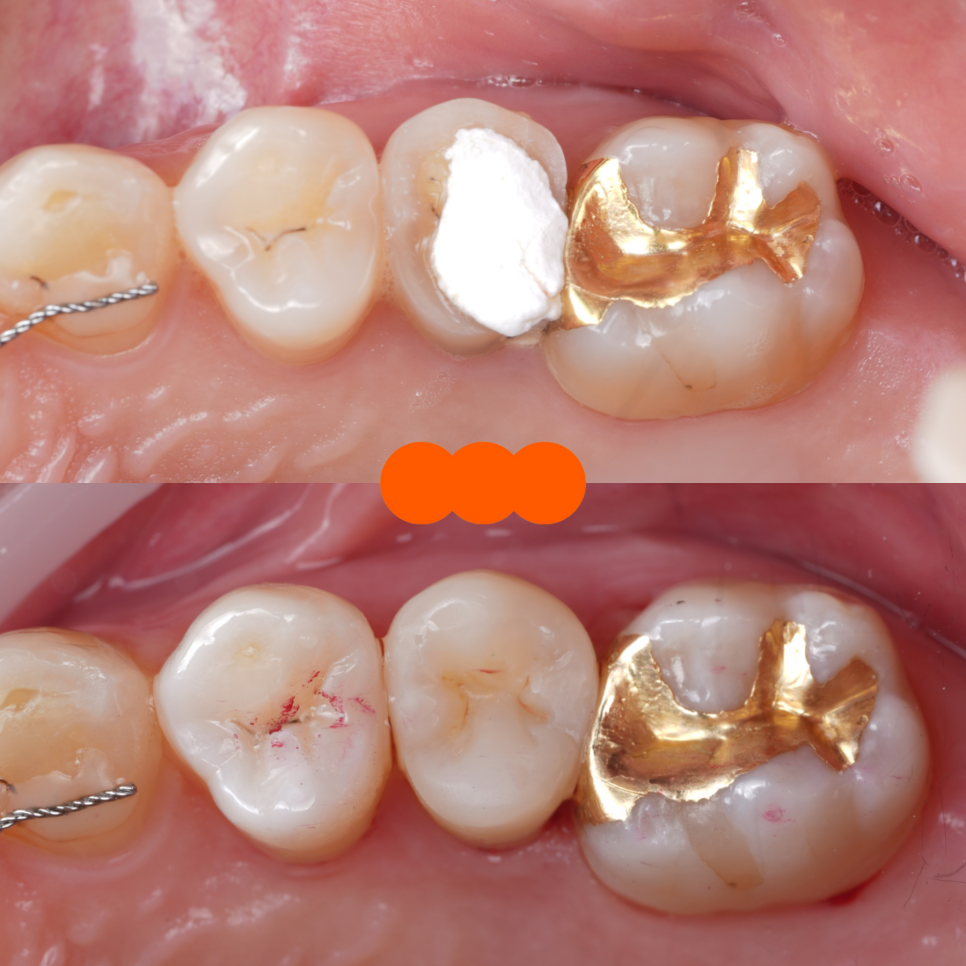

촬영일 : 251124

실제로 꽤 넓은 부분도 레진으로 치료해서 오랫동안 잘 쓰시는 분들이 많습니다.

기존에 남아 있던 충전물·임시재를 깨끗이 제거해서 충치와 재료 경계를 깔끔하게 정리했고 안쪽 바닥은 보험이 되는 재료(GI)로 두 면을 먼저 채워 뼈대(바탕)를 만들어 주기로 했죠.

이후 그 위에 신경치료를 위해 만든 구멍을 메우는 작업(코어, Core)와 함께 씹는 면 전체를 포괄적으로 덮는 레진 빌드업으로 형태(교두와 벽)를 다시 만들어 드렸어요.

쉽게 말하면 안쪽은 단단하게 기초를 다지고 바깥은 레진으로 치아 본래 모양과 기능을 다시 만들어 드린 것이라고 생각하시면 됩니다.

촬영일 : 251124 / 251124